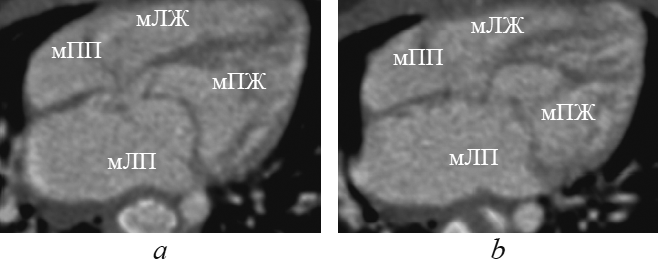

Для морфологически правого желудочка характерны следующие анатомические признаки трабекулярного отдела: небольшое количество грубых трабекул с тонким плотным слоем миокарда, при этом трабекулы разделены глубокими желобками, простирающимися вплоть до эпикарда; характерно наличие модераторного пучка [1, 2, 4, 9, 14] (рис. 3).

Рис. 3. Реформация приточных отделов желудочков. мЛЖ — морфологически левый желудочек; мЛП — морфологически левое предсердие; мПЖ — морфологически правый желудочек; мПП — морфологически правое предсердие

Fig. 3. Supply ventricles division reformation. мЛЖ – morphologically left ventricle; мЛП – morphologically leftatrium; мПЖ – morphologically right ventricle; мПП – morphologically rightatrium

При транспозиции магистральных артерий топология желудочков относительно расположения сердца в грудной полости следующая: морфологически правый желудочек располагается справа, спереди и снизу относительно морфологически левого желудочка (рис. 4).

Рис. 4. Реформация приточных отделов желудочков при транспозиции магистральных артерий. мЛЖ — морфологически левый желудочек; мЛП — морфологически левое предсердие; мПЖ — морфологически правый желудочек; мПП — морфологически правое предсердие

Fig. 4. Supply ventricles division reformation in great arteries transposition. мЛЖ – morphologically left ventricle; мЛП – morphologically left atrium; мПЖ – morphologically right ventricle; мПП – morphologically right atrium

При корригированной транспозиции магистральных артерий морфологически правый желудочек располагается слева и сзади от морфологически левого желудочка (рис. 5, 6).

Рис. 5. Реформация приточных отделов желудочков при корригированной транспозиции магистральных артерий. мЛЖ — морфологически левый желудочек; мЛП — морфологически левое предсердие; мПЖ — морфологически правый желудочек; мПП — морфологически правое предсердие

Fig. 5. Supply ventricles division reformation in corrected great arteries transposition. мЛЖ – morphologically left ventricle; мЛП – morphologically left atrium; мПЖ – morphologically right ventricle; мПП – morphologically right atrium

Рис. 6. Реформация приточных отделов желудочков при корригированной транспозиции магистральных артерий. мЛЖ — морфологически левый желудочек; мЛП — морфологически левое предсердие; мПЖ — морфологически правый желудочек; мПП — морфологически правое предсердие

Fig. 6. Supply ventricles division reformation in corrected great arteries transposition. мЛЖ — morphologically left ventricle; мЛП — morphologically left atrium; мПЖ — morphologically right ventricle; мПП — morphologically right atrium

При обычном расположении морфологически правое предсердие находится справа от морфологически левого предсердия. При обратном расположении морфологически правое предсердие находится слева от морфологически левого предсердия. Положение предсердий почти всегда связано с положением внутренних органов, но не зависит от положения желудочков или магистральных артерий. При транспозиции (см. рис. 4) и корригированной транспозиции (см. рис. 5, 6) взаимное расположение предсердий, как правило, обычное.